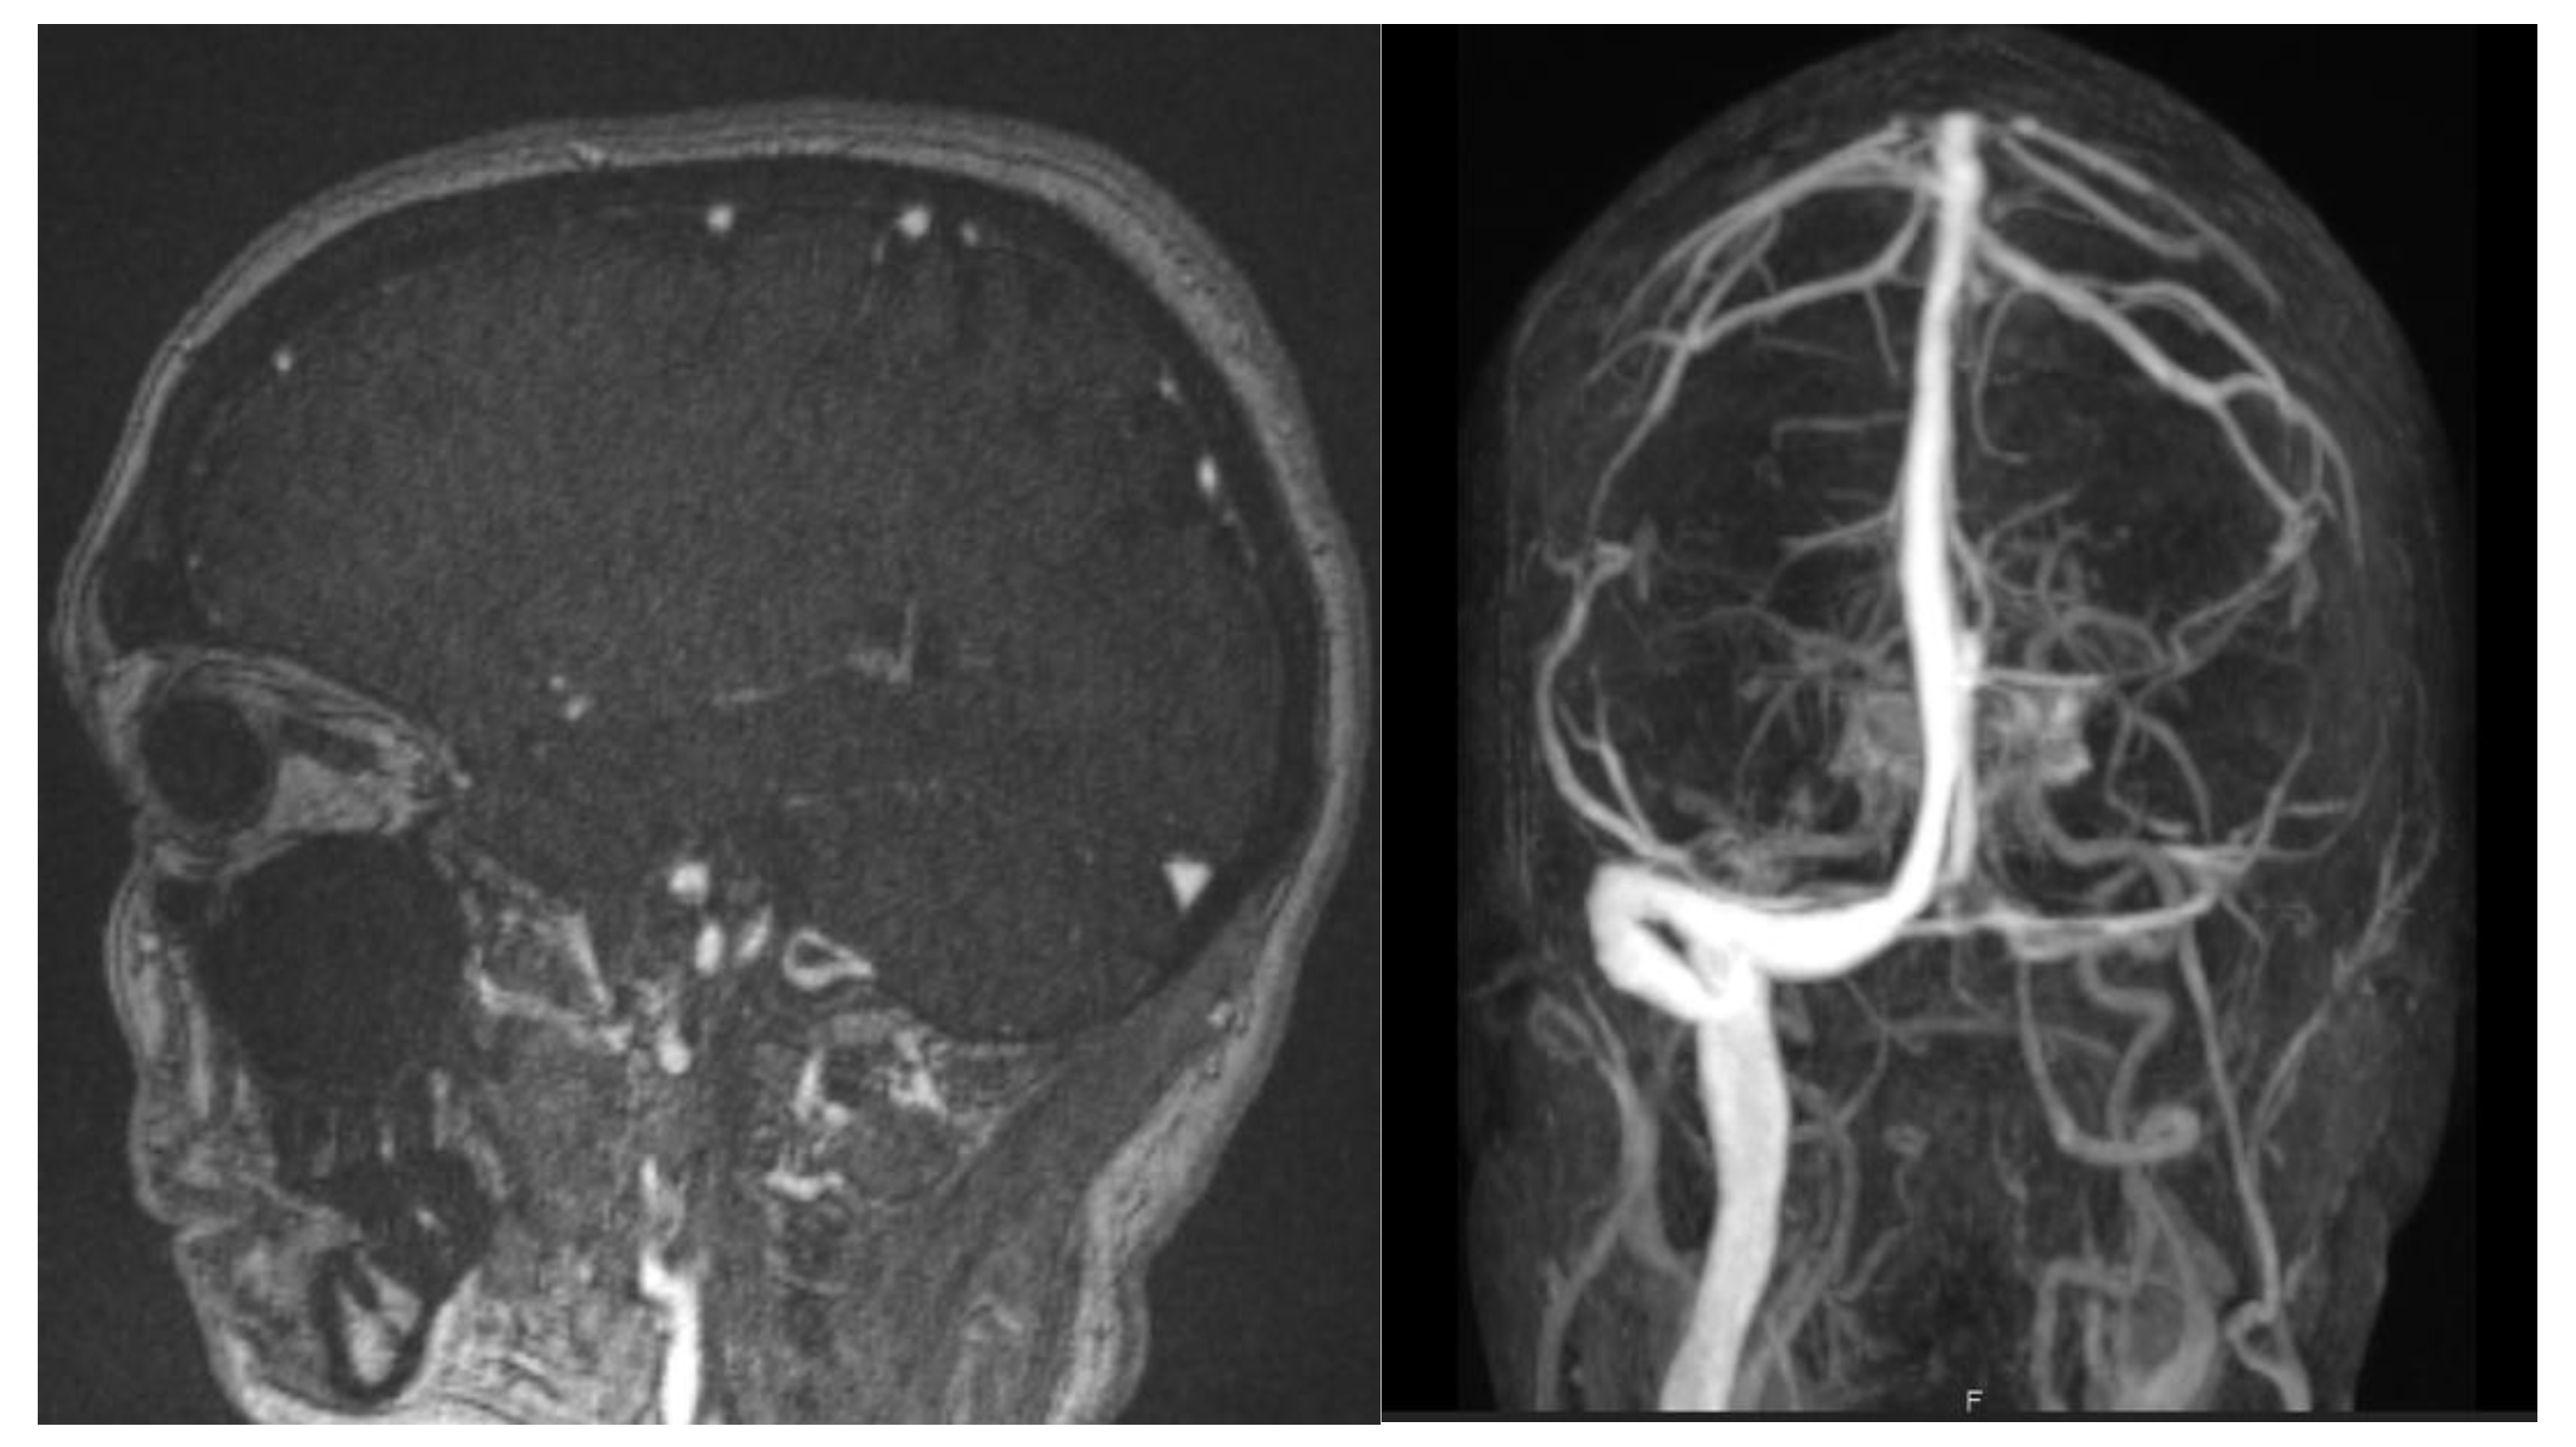

| F | 52 | Yes (Astra Zeneca) | 5 miscarriages, SAPL-negative | 18 | Right lateral and sigmoid sinus thrombosis | LMWH then apixaban | None | Discharged with no complications |